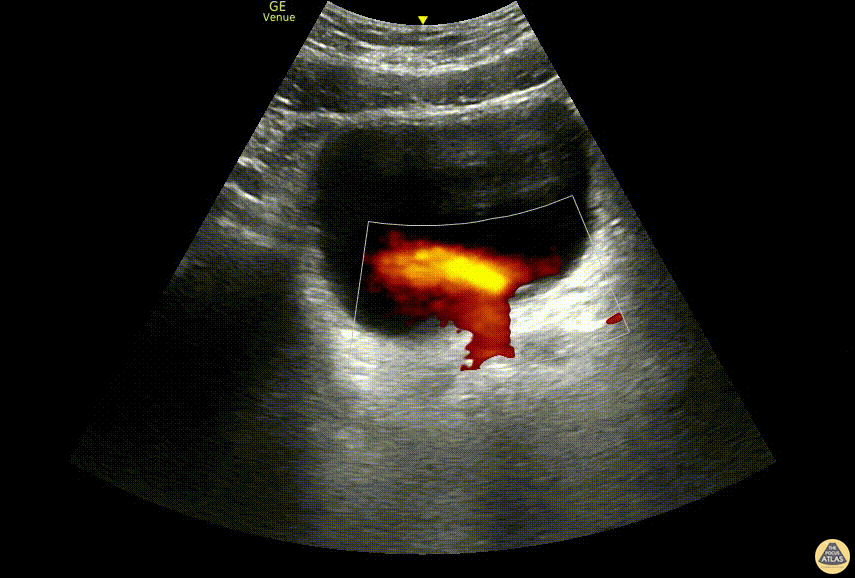

Renal/GU - "Light Saber Sign” Ureteral Jets

A 48-year old male presented to the ED with lower abdominal pain and flank pain presented to the ED. A renal and bladder point-of-care ultrasound was done to evaluate for hydronephrosis which revealed distinct bilateral ureteral jets, which we dubbed the “light saber sign.” Dr. Jannie Bolotnikov, PGY-1, Denver Health Emergency Medicine Residency Dr. Fred Milgrim, Ultrasound Fellow, Denver Health Emergency Medicine